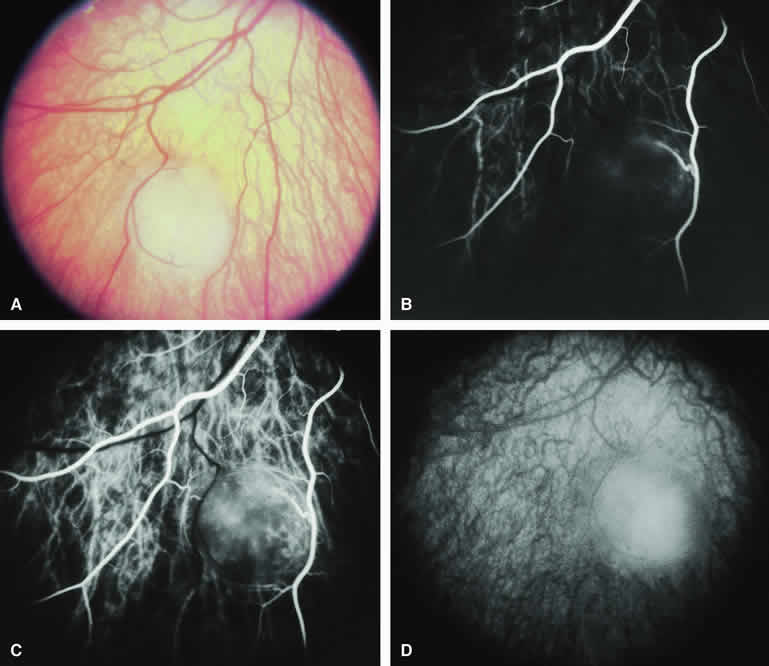

Typical Melanotic Choroidal Nevus

Fluorescein angiography of a typical choroidal nevus with bland surface features (see Fig. 1) shows the entire lesion to be hypofluorescent relative to the adjacent uninvolved choroid throughout the study. No large-caliber choroidal blood vessels are usually identifiable within the lesion. The retinal vasculature overlying the lesion appears well defined and normal on fluorescein angiography.

ICG angiography of a typical melanotic choroidal nevus (see Fig. 2) shows better definition of the basal area of the lesion than does fluorescein angiography. The entire lesion appears completely and uniformly dark throughout the ICG angiogram. Only the larger retinal blood vessels overlying the nevus are usually demonstrated on ICG angiography.